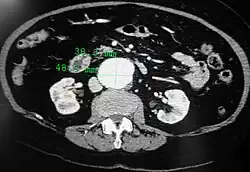

A transverse contrast enhanced CT scan demonstrating an abdominal aortic aneurysm of 4.8 by 3.8 cm -